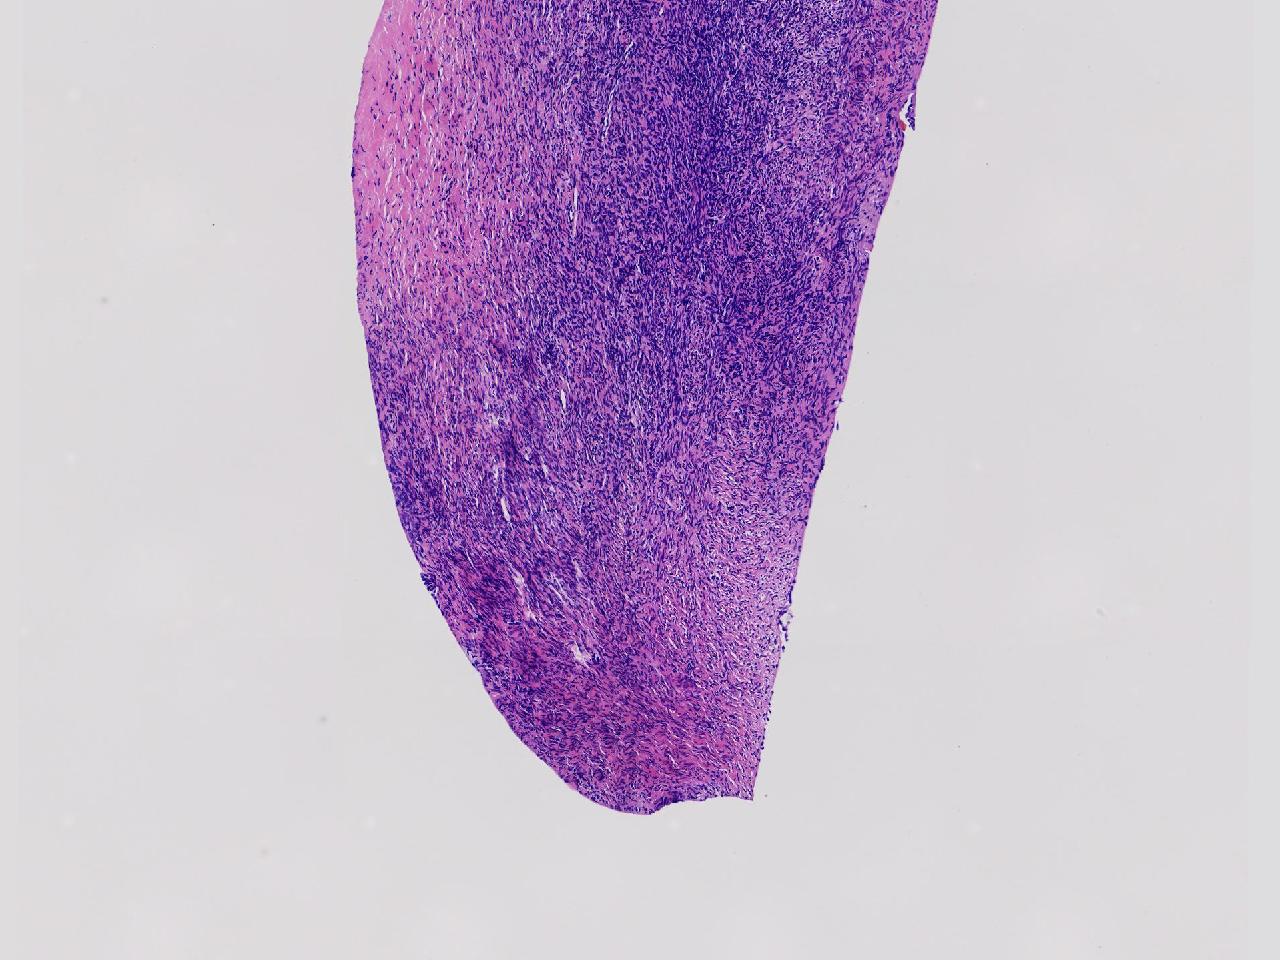

卵巢颗粒状突起活检。

女,34岁。右侧输卵管 异位妊娠,宫腔镜下见左侧卵巢颗粒状突起,取活检1块。

左侧卵巢颗粒状突起活检

灰白色不整形软组织1块,至今0.2厘米。

妊娠黄体瘤? 卵巢间质增生?

未见妊娠黄体瘤改变,见卵巢间质纤维增生。

卵巢间质纤维增生